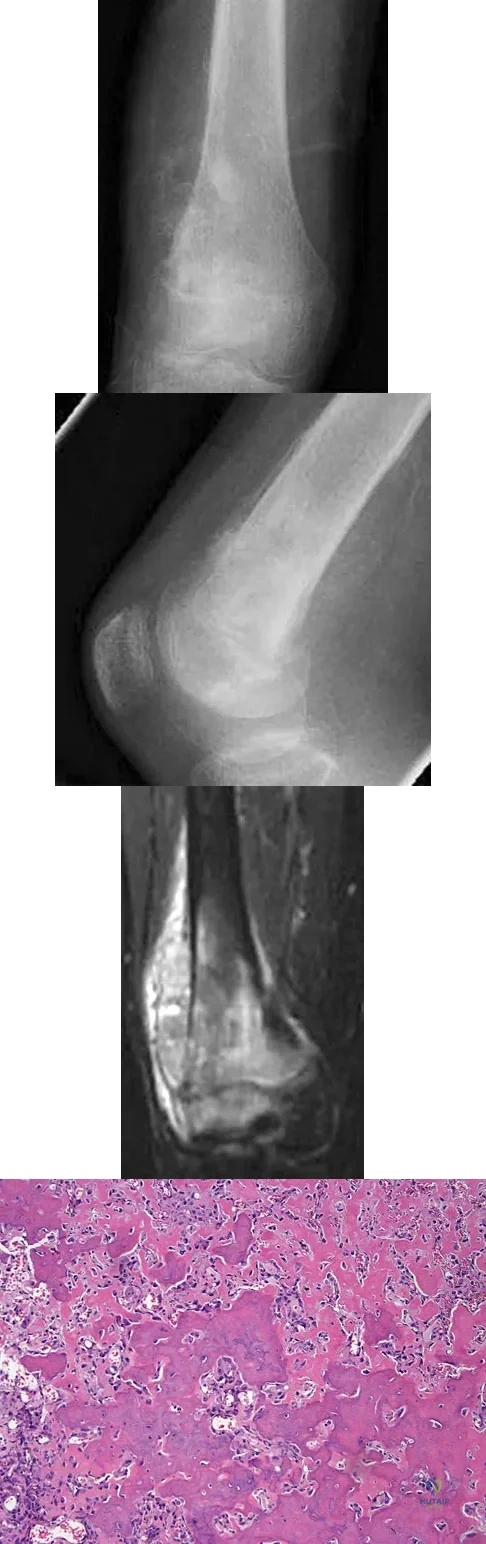

A 7-year-old girl has had a painful forearm for the past 2 months. Examination reveals fullness on the volar aspect of the forearm. Radiographs and an MRI scan are shown in Figures 42a through 42c. Biopsy specimens are shown in Figures 42d and 42e. What is the most likely diagnosis?

A 16-year-old girl has had painless swelling in her posterior left arm for the past 4 months. A radiograph, MRI scans, and an incisional biopsy specimen are shown in Figures 43a through 43d. What is the cytogenetic translocation most commonly associated with this tumor?

A healthy 16-year-old boy has had increasing pain in the right knee for the past 3 months. Examination reveals warmth and swelling around the distal femur. Radiographs and an MRI scan are shown in Figures 51a through 51c, and a biopsy specimen is shown in Figure 51d. What is the most likely diagnosis?